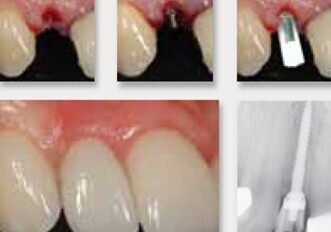

Immediate Smile bridge: CAD/CAM restorations for immediate loading

CASE REPORT: Reduction guide facilitated tooth extractions, bone reduction and guided implant placement with immediate prosthetic loading. In our view, the ...